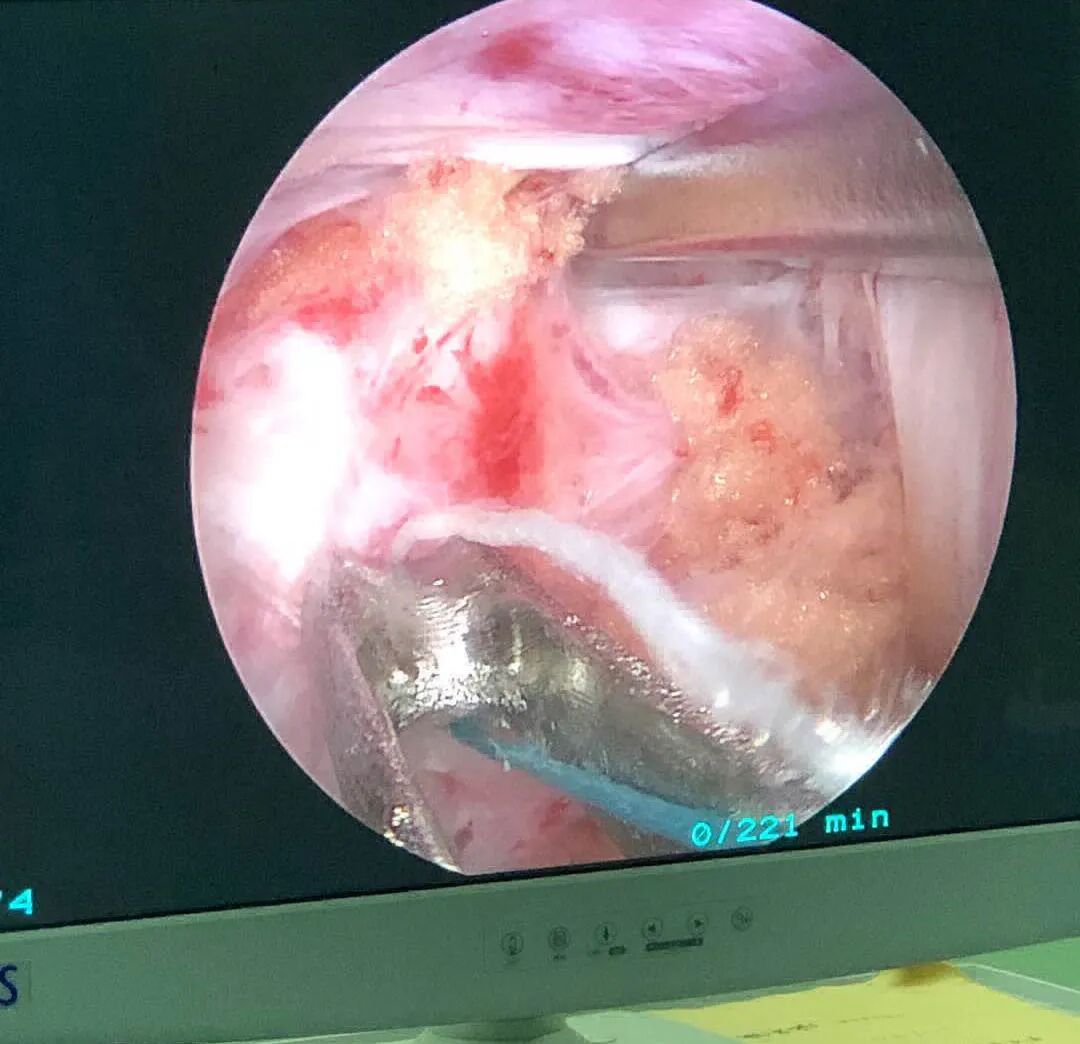

術(shù)中圖片

鏡下影像圖片

? ? ?手術(shù)經(jīng)過(guò)、術(shù)中發(fā)現(xiàn)的情況及處理,患 者麻醉成功后取俯臥位,c臂適視確認(rèn)L5/S1間隙左側(cè)觀(guān)察通道及工作通道的體表位置,選擇L5椎板下緣及S1椎板上緣分別作為觀(guān)察通道及工作通道的定位點(diǎn)。常規(guī)消毒鋪巾,貼皮膚保護(hù)膜。沿定位點(diǎn)分別作長(zhǎng)約1cm的縱行切口。置入U(xiǎn)BE肌肉剝離器及內(nèi)窺鏡,透視確認(rèn)雙通道位置及深度滿(mǎn)意。剝離器及擴(kuò)張導(dǎo)管進(jìn)一步將肌內(nèi)從基部分離, 以利于顯露關(guān)節(jié)突面及椎板間間隙。內(nèi)窺鏡下射頻刀頭清理椎板間隙表面肌肉組織,顯露上下椎板,使用椎板咬骨鉗和磨鉆處理椎板邊緣及關(guān)節(jié)突關(guān)節(jié),尋找黃韌帶于椎板破口位置,刮匙將韌帶與椎板邊緣間進(jìn)行修整和分離。使用直骨刀將L5椎板下緣及S1椎板上緣、關(guān)節(jié)突內(nèi)惻緣部分切除行擴(kuò)大處理,進(jìn)一步去除黃韌帶,行側(cè)隱窩減壓處理。剝離神經(jīng)顯露突出的間盤(pán),髓核鉗摘除突出髓核組織,顯露探查見(jiàn)硬膜囊及神經(jīng)根臧壓滿(mǎn)意。鏡下觀(guān)察無(wú)活動(dòng)性出血,神經(jīng)根松弛,滋養(yǎng)血管血運(yùn)恢復(fù),硬膜囊搏動(dòng)好:術(shù)畢徹底止血,退出內(nèi)鏡及工作通道,縫合刀口。手術(shù)順利,麻醉滿(mǎn)意,術(shù)中病人患者生命體征平穩(wěn),無(wú)特殊不適,術(shù)中出血約20ml,術(shù)后安返病房。